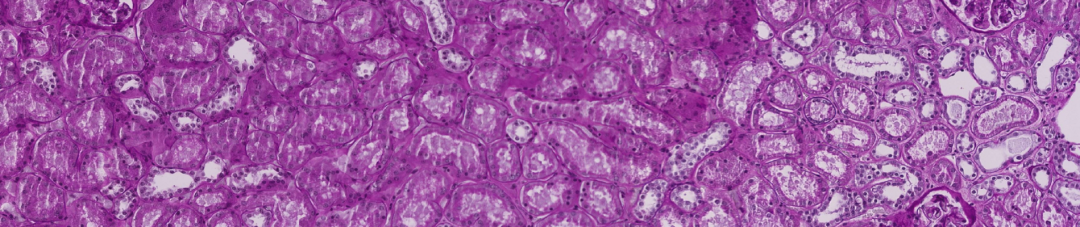

内容简介

该竞赛的目标是分割微血管结构的实例,包括毛细血管、小动脉和小静脉。参与者需创建一个模型,并在来自健康人体肾脏组织切片的2D PAS染色组织学图像上进行训练。

该比赛需要用到语义分割技术。